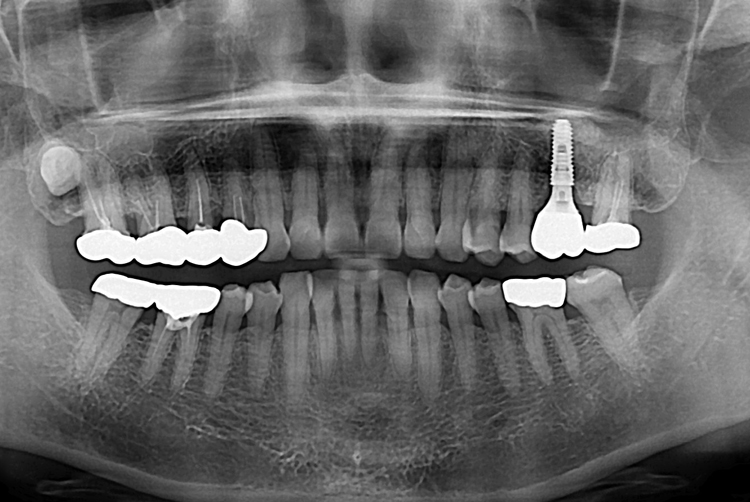

[임플란트] 어금니 임플란트

치료전 : 2017-08-22